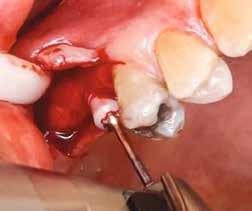

Klinikai munkamenet

Kezdésnek atraumatikusan eltávolítottuk az érintett fogakat (3. ábra), ezt követően előkészítettük az alveolust és azonnali implantációt végeztünk a megfelelő implantátummal (4. ábra). Amennyiben a behajtási nyomaték nagyobb volt, mint 35 Ncm, az implantátumra azonnal felcsavaroztuk az előre legyártott csavarozható koronát. Ehhez a beavatkozáshoz az előfeltételek: sértetlen posztextrakciós alveolus, egészséges lágyszövetek, gyulladásmentes környezet, valamint együttműködő páciens (5). A háromdimenziós tervezés nélkülözhetetlen az alább bemutatott munkamenet kivitelezéséhez (6–8). Csak a sablon által vezetett implan-

3. ábra: Atraumatikus fogeltávolítás.

4. ábra: Azonnali implantáció.